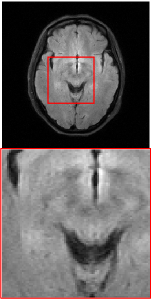

Figure 5 provides the qualitative comparison of the various methods on the four datasets at a scale of 4. The top, second, third, and bottom rows are the SR results under the FastMRI, clinical brain, clinical tumor and clinical pelvic datasets, respectively. The red boxes indicate the zoom-in region of complicated anatomical structures along with their corresponding error maps. Note that the brighter textures in the error maps, the lower the quality of the reconstructed images. As can be seen, compared to methods based on Transformers and CNNs, diffusion-based methods like DisC-Diff and DiffMSR (Ours) are capable of reconstructing high-realistic images with promising reconstruction metric scores (PSNR and SSIM). Nevertheless, while DisC-Diff can reconstruct high-precision MR images, it does not preserve the structure present in the original HR images, introducing some additional information that can affect medical diagnosis. In contrast, our method combines DM and PLWformer, which can preserve the original image’s structure while restoring high-frequency information.

In this section, we present more visual qualitative comparisons. Figures 8, 9, 10, and 11 show the reconstruction results of each method in FastMRI, clinical brain, clinical tumor, and clinical pelvic, respectively. As can be seen, although DisC-Diff can reconstruct MR images with high-frequency information, it fails to preserve the structure and content of the original Target HR image effectively, resulting in image distortion. In contrast, our proposed DiffMSR can restore high-frequency information while preserving the structure of the original HR image, indicating the effectiveness of the joint use of DM and PLWformer.